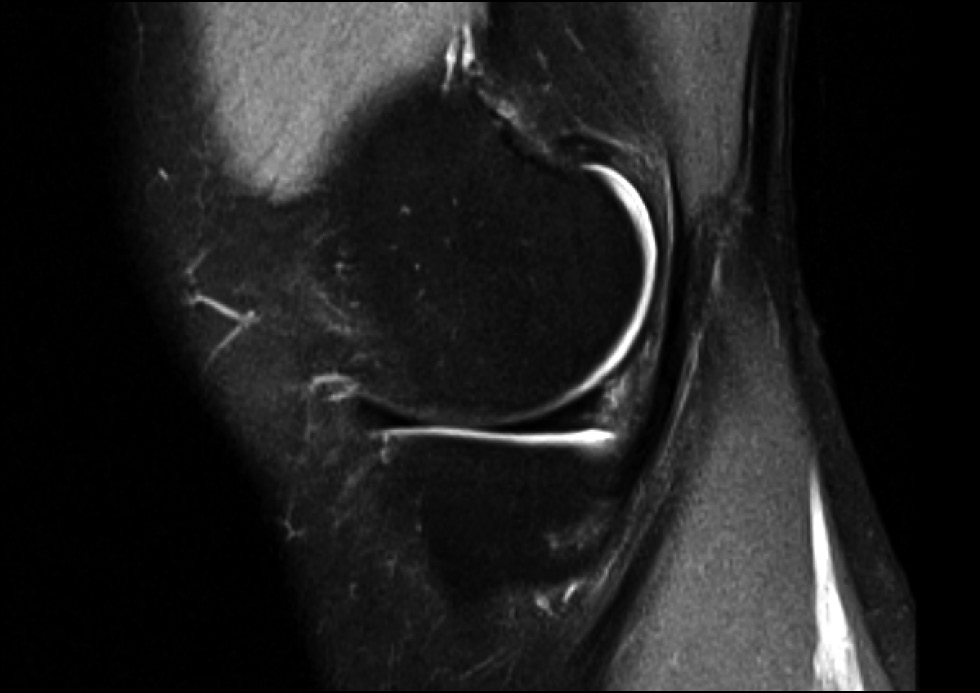

The results of treatment of patients are presented in Table 2 and in Figures 5 and 6. According to the VAS, Lequesne, Lysholm, KSS scales, and WOMAC index, all parameters improved, degree of pain syndrome decreased, and functional parameters increased.

Fig. 6. MRI of the patient 6 months after the platelet-rich plasma (PRP) procedure.

The issues of treatment of damage to the inner layer of the knee joint menisci, which does not extend to the articular surface, remain. In our study, all rating scales demonstrated an improvement in performance. In addition, according to MRI data, after 6 months, no progression of the degenerative process in the menisci was observed. We believe that our method can be the first step in the treatment of this pathology. We obtained a patent for this treatment method (RU No. 2747589 dated May 11, 2021).